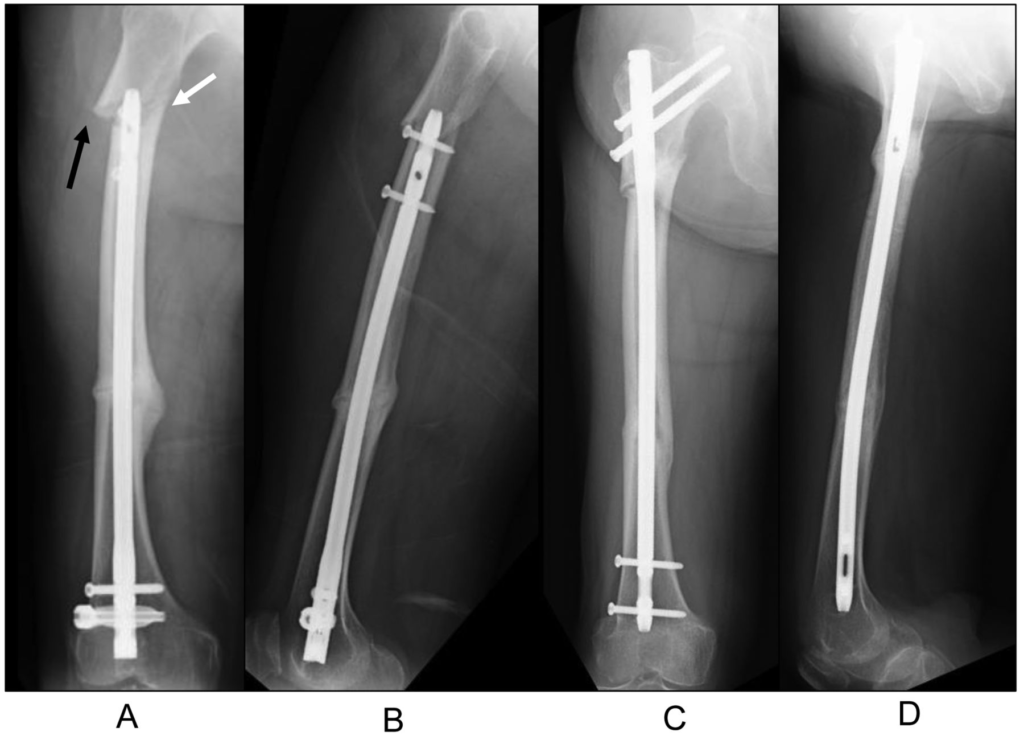

A femoral nail, also known as an intramedullary nail or IM nail, is a metal rod or nail that is inserted into the medullary canal of the femur (thigh bone) to stabilize and promote the healing of fractures. It serves as an internal fixation device that offers several advantages over traditional methods of fracture treatment.

- Nail Insertion: The femoral nail is inserted into the canal and positioned to bridge the fracture.

- Locking Screws: Additional locking screws may be used at both ends of the nail to secure it in place.